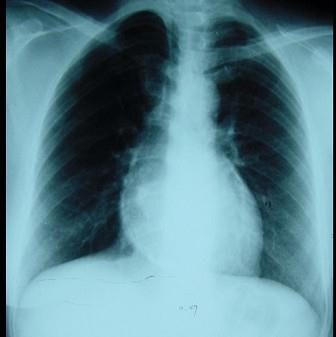

女性,46岁。间断胸痛4年,胸闷2年,外院诊断为“风湿性心脏病”。入院查体:血压110/65mmHg,颈静脉无充盈,心律75次/分,未闻及杂音,双下肢浮肿...

问题 女性,46岁。间断胸痛4年,胸闷2年,外院诊断为“风湿性心脏病”。入院查体:血压110/65mmHg,颈静脉无充盈,心律75次/分,未闻及杂音,双下肢浮肿,肝脏肋下2cm。 该病的病理和病理生理为 ( )